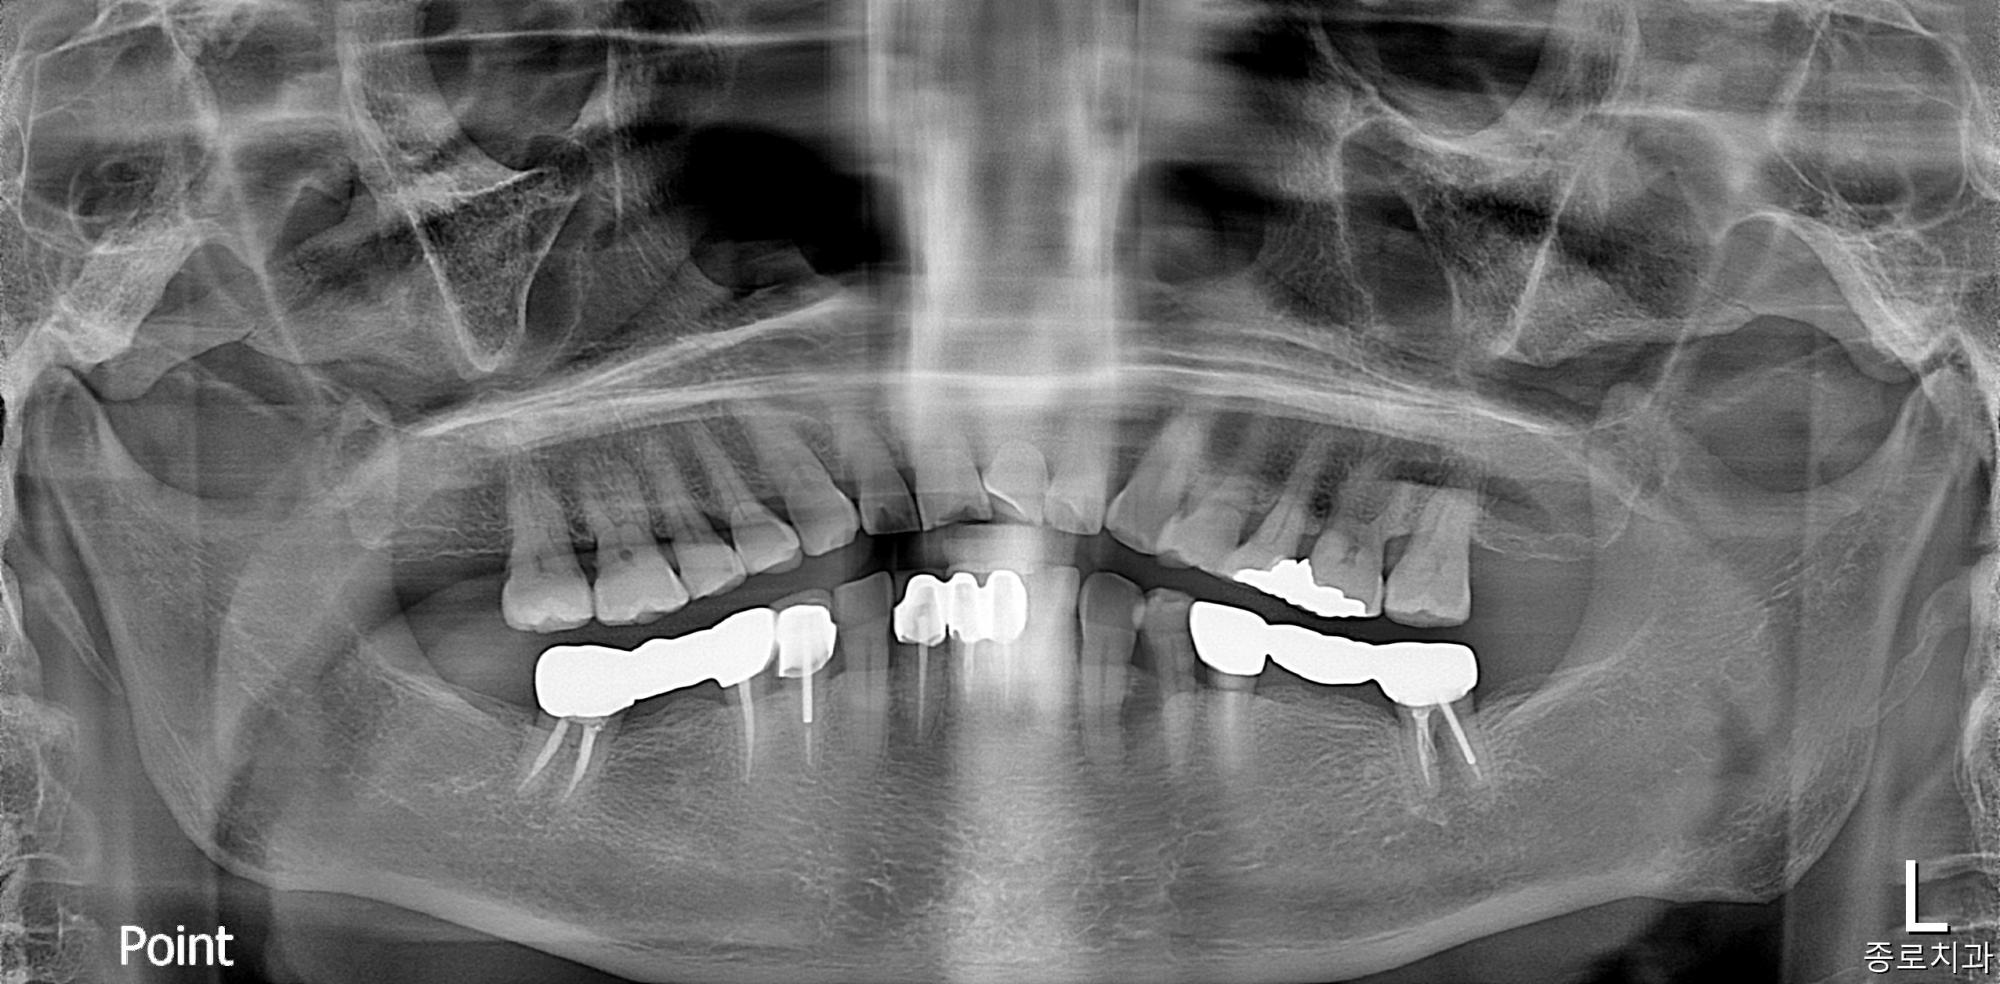

전/후사진

전/후 사진갤러리